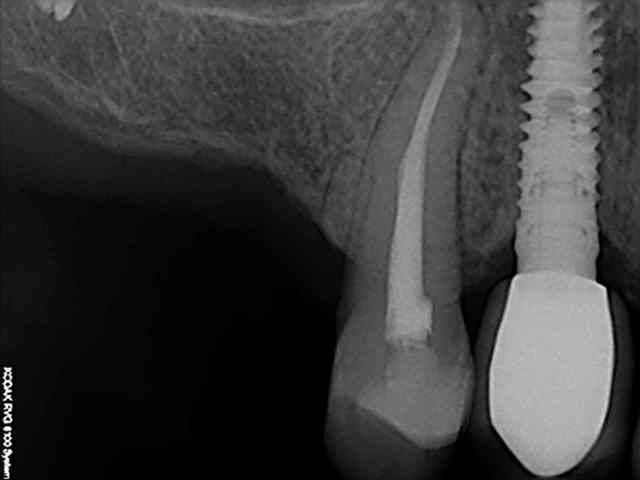

> Jolie, tu as un radio post-op ?

aussitôt demandé, aussitôt fait !!

(j+1 an)

tu as perdu pas mal d'os!!